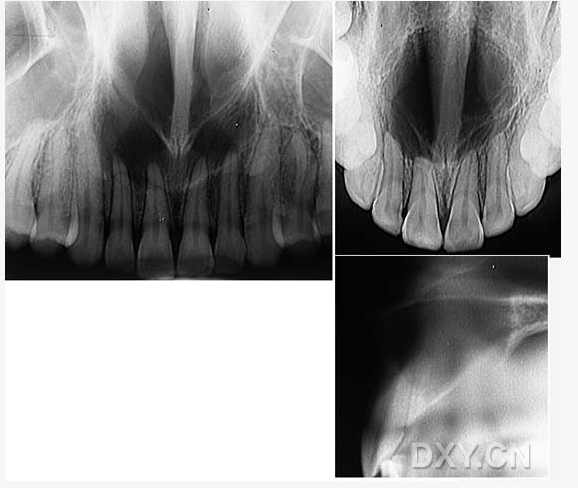

鼻鄂囊腫

球狀上頜囊腫

含牙囊腫

球狀上頜囊腫    含牙囊腫

鼻腭囊腫